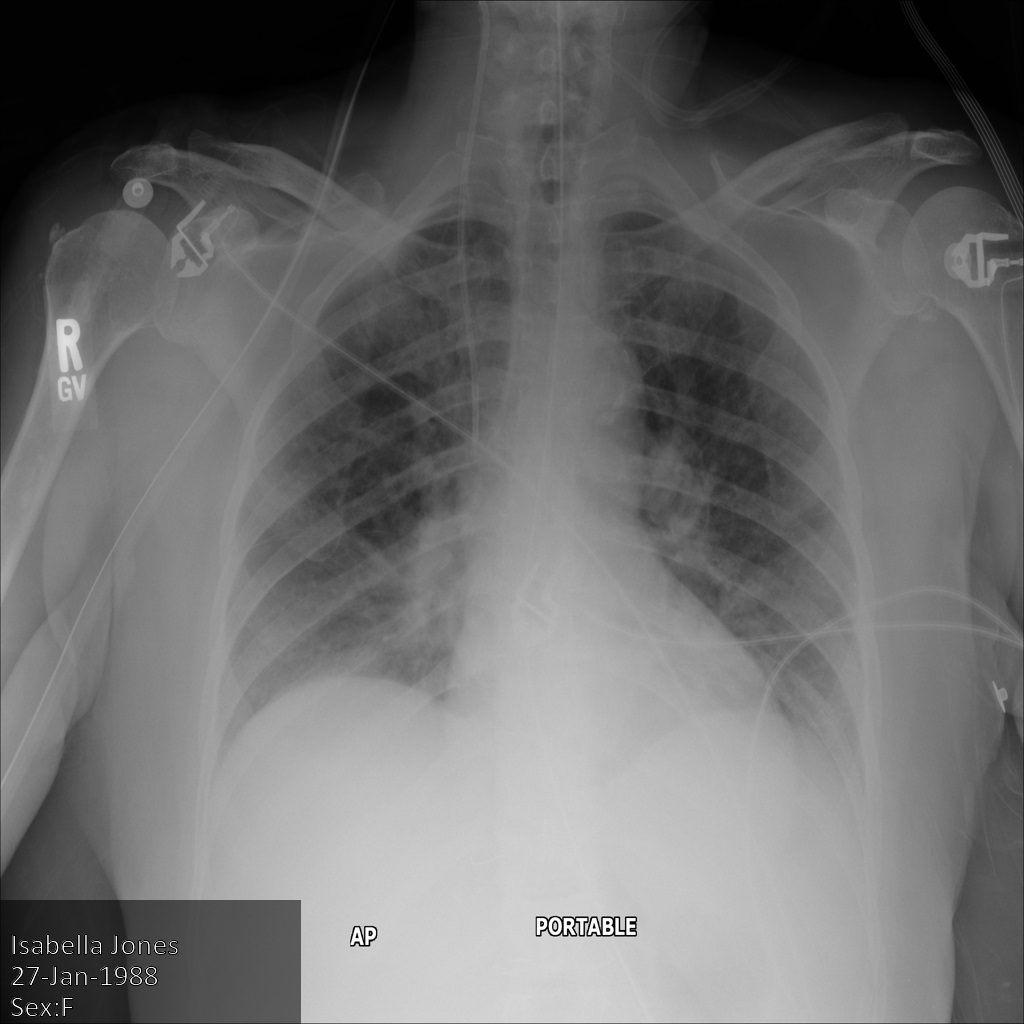

L'image suivante montre une radiographie non masquée d'un patient :

Une fois l'image envoyée à l'API Cloud Healthcare à l'aide de l'option REDACT_SENSITIVE_TEXT, elle apparaît comme suit :

Vous pouvez constater que les événements suivants se sont produits :

- Le paramètre

PERSON_NAMEen bas à gauche de l'image a été masqué. - Le paramètre

DATEen bas à gauche de l'image a été masqué.

Le sexe du patient n'a pas été masqué, car il n'est pas considéré comme du texte sensible selon le paramètre infoTypes DICOM par défaut.